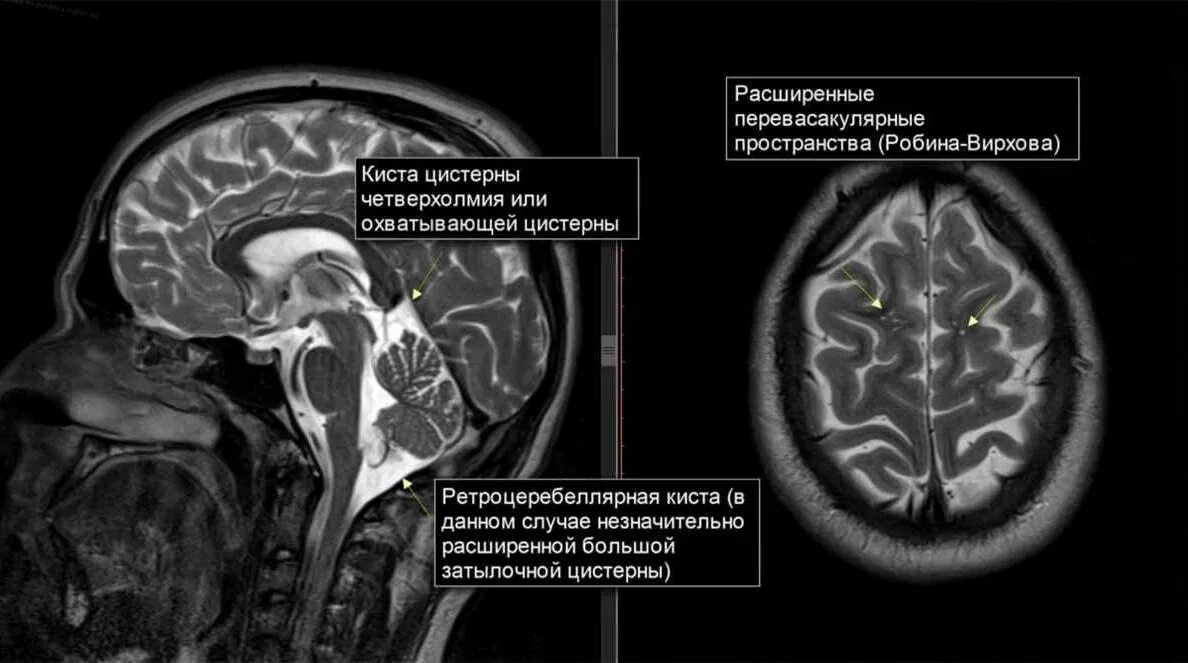

Расширение ликворосодержащих пространств